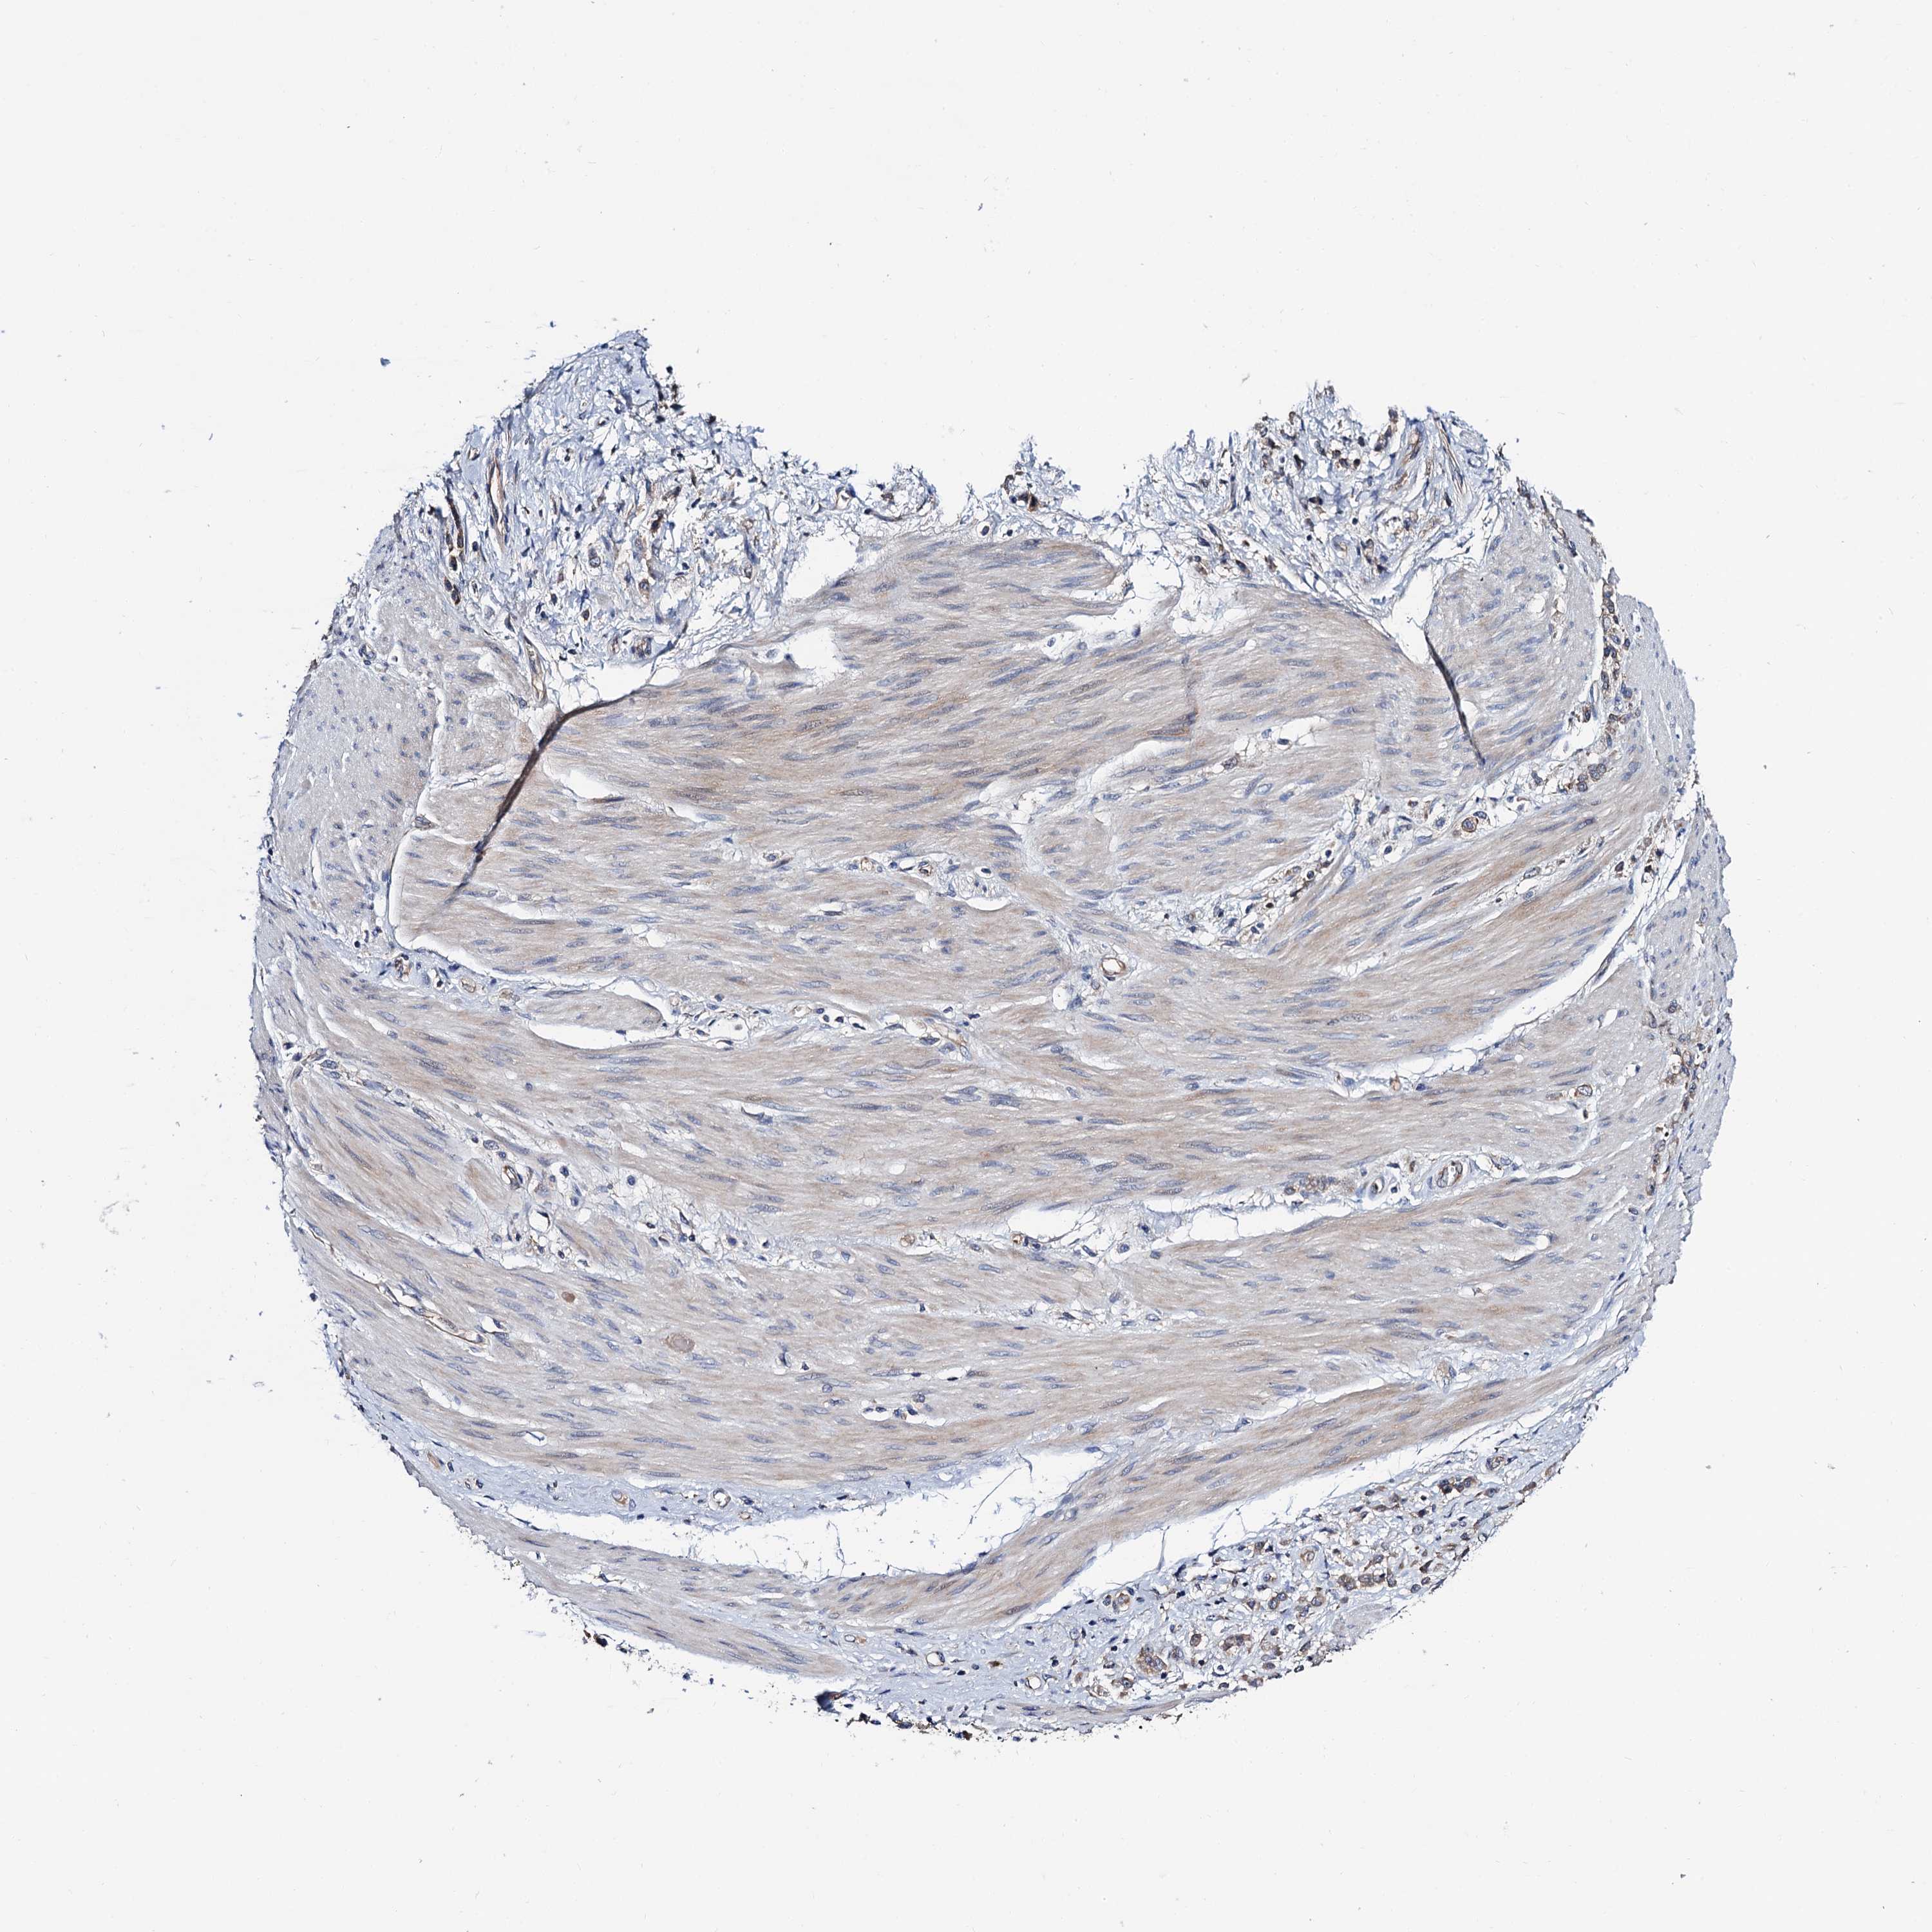

STOMACH CANCER - Protein expressioni

A mouse-over function shows sample information and annotation data. Click on an image to view it in a full screen mode. Samples can be filtered based on level of antibody staining by selecting one or several of the following categories: high, medium, low and not detected. The assay and annotation is described here.

Note that samples used for immunohistochemistry by the Human Protein Atlas do not correspond to samples in the TCGA dataset.

Antibody stainingi

Antibody staining in the annotated cell types in the current human tissue is reported as not detected, low, medium, or high, based on conventional immunohistochemistry profiling in selected tissues. This score is based on the combination of the staining intensity and fraction of stained cells.

Each image is clickable and will lead to virtual microscopy that enables deeper exploration of all samples and also displays staining intensity scores, fraction scores and subcellular localization as well as patient and tissue information for each sample.

Antibody HPA039901

Antibody HPA040006

Staining

High

Medium

Low

Not detected

Intensity

Strong

Moderate

Weak

Negative

Quantity

>75%

75%-25%

<25%

None

Location

Nuclear

Cytoplasmic/membranous

Cytoplasmic/membranous,nuclear

Adenocarcinoma, NOS

Adenocarcinoma, High grade